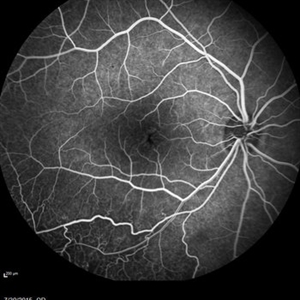

Retinal Dystrophy of 24-Year-Old Male Early FA OD

Nov 25 2015 by Zach Dupureur

Fluorescein angiography of a 24-year-old male. Juvenile retinoschisis on OCT. FA shows outer retinal staining. Could be associated with Goldmann Farve Syndrome.

Condition/keywords: Goldmann-Favre Syndrome, juvenile retinoschisis, retinal dystrophy